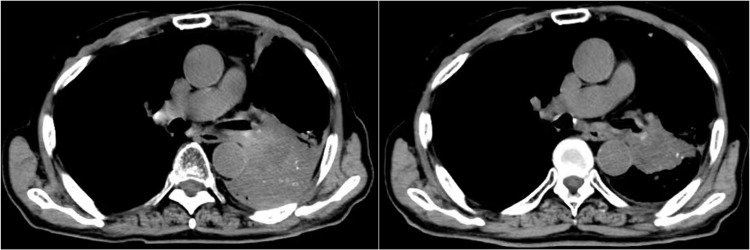

Methods: This retrospective study included 56 patients with advanced NSCLC treated with systemic treatment previously. Patients included were treated with anlotinib plus PD-1 inhibitors in clinical practice. Therapeutic outcomes of the patients were evaluated radiologically using target lesions, and the prognostic outcomes were generated by follow-up. Adverse reactions experienced throughout the treatment were documented and analyzed.

Results: Between August 2018 and November 2022, 56 patients with advanced NSCLC were eligible to participate in this study consecutively. Therapeutic outcomes resulted in an overall response rate of 28.6% [95% confidence interval (CI): 17.3%-42.2%] and a disease control rate of 91.1% (95% CI: 80.4%-97.0%). Furthermore, this combination regimen among the 56 patients yielded a median progression-free survival (PFS) of 6.5 months (95% CI: 4.81-8.19) and a median overall survival (OS) of 15.8 months (95% CI: 10.23-21.37), respectively. And the median duration of response (DoR) among patients who responded was 8.3 months (95% CI: 4.38-12.22). Additionally, adverse reactions of all grades throughout the treatment were observed in 50 patients (89.3%), and adverse reactions of grade ≥3 were detected in 23 patients (41.1%). Fatigue, hypertension, diarrhea, nausea, and vomiting were the most common adverse reactions. Association analysis between PFS and baseline characteristic subgroups indicated that ECOG score and number of metastatic lesions might be potential predictors of PFS in the exploratory analysis.